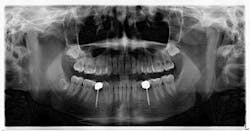

Hygiene. It can be agreed upon that if an implant can’t be kept clean, then the potential for failure and difficulties rise exponentially. A 90-degree angle between the implant and crown is virtually impossible to keep clean and maintain. As amazing as some hygienists are, it is impractical to expect that a curette can get into that space to clean it without making hamburger of the tissue. The implants were cemented on, so they are not easily retrievable. The emergence profile is nonexistent. Do natural teeth look like this? I would submit that when restoring implants, it is our job to mimic the shape and emergence profile of natural teeth as closely as possible. When we don’t, then we lose the inherent cooperation and benefits that the tissue can provide. To help the parents understand this concern, I showed them an example of a traditional implant vs. the “pumpkin on a toothpick” implant. The side-by-side comparison spoke for itself.